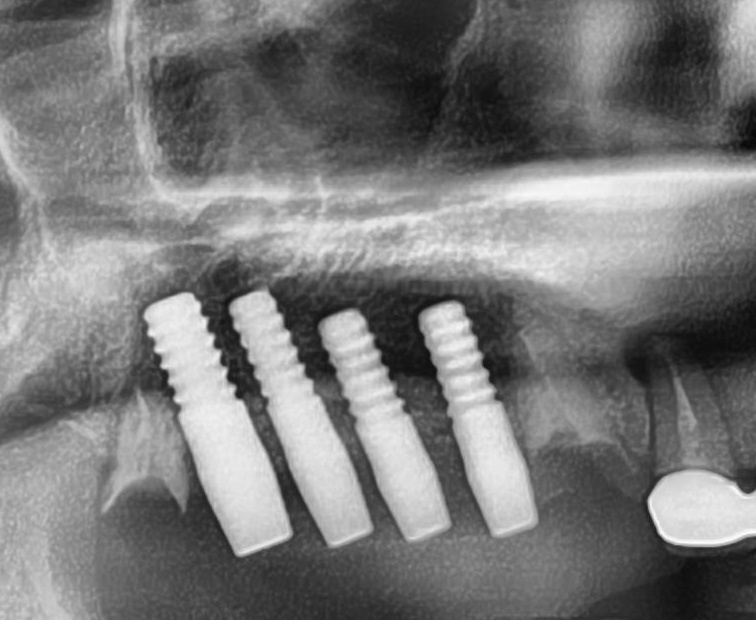

しっかりとインプラント埋め込まれた後は、動揺がないか、噛んだ時に当たらないかなどを確認して、最後にパノラマ写真を撮影して今回のオペは終了となりました。